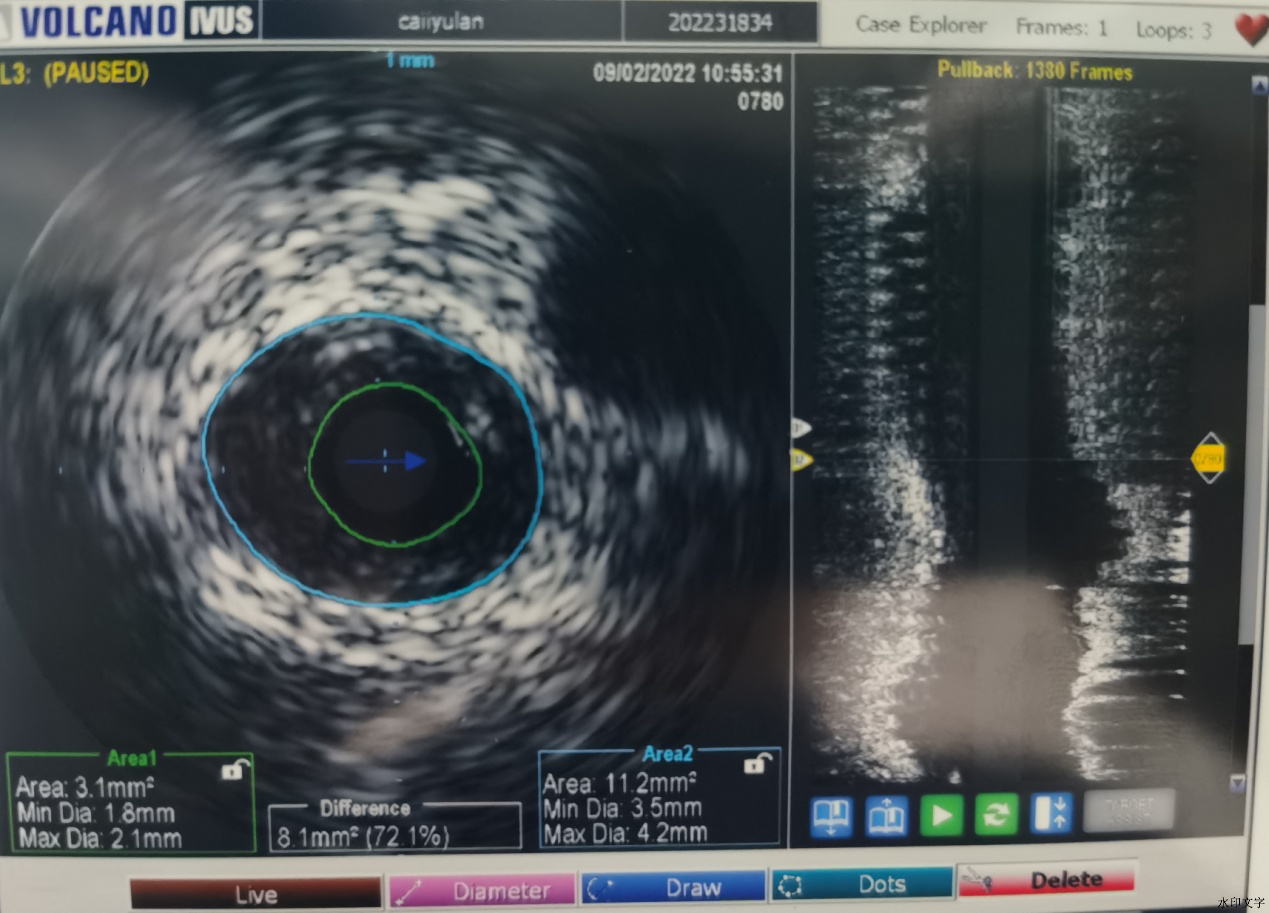

蔡先生1年前曾在我院冠脉CTA检查提示LAD近段轻度狭窄,日前胸闷症状仍有反复,在居住的当地动态心电图检查,捕捉到ST段动态性改变,为进一步诊疗于9月1日收住我院心内科。入院的第二天行冠脉造影发现前降支中段狭窄80%,并给予了IVUS检查,提示狭窄部位为脂质斑块,该斑块易发生炎症、破裂,一旦发展会导致血管的梗塞;且有效管腔面积 3.1mm2(MIN DIA .8MM MAXDIA 2.1MM 斑块负荷8.1mm2 72.1% EEM 11.2MM2 MIN DIA 3.5MM MAX DIA 4.2MM)。

根据IVUS的测出的血管管腔大小给予植入3.0*30mm药物洗脱支架,取3.25*12mm非顺应性球囊送至左前降支病变段支架内,在支架内以18-20atm扩张塑形。再次行IVUS检查证实支架贴壁良好。